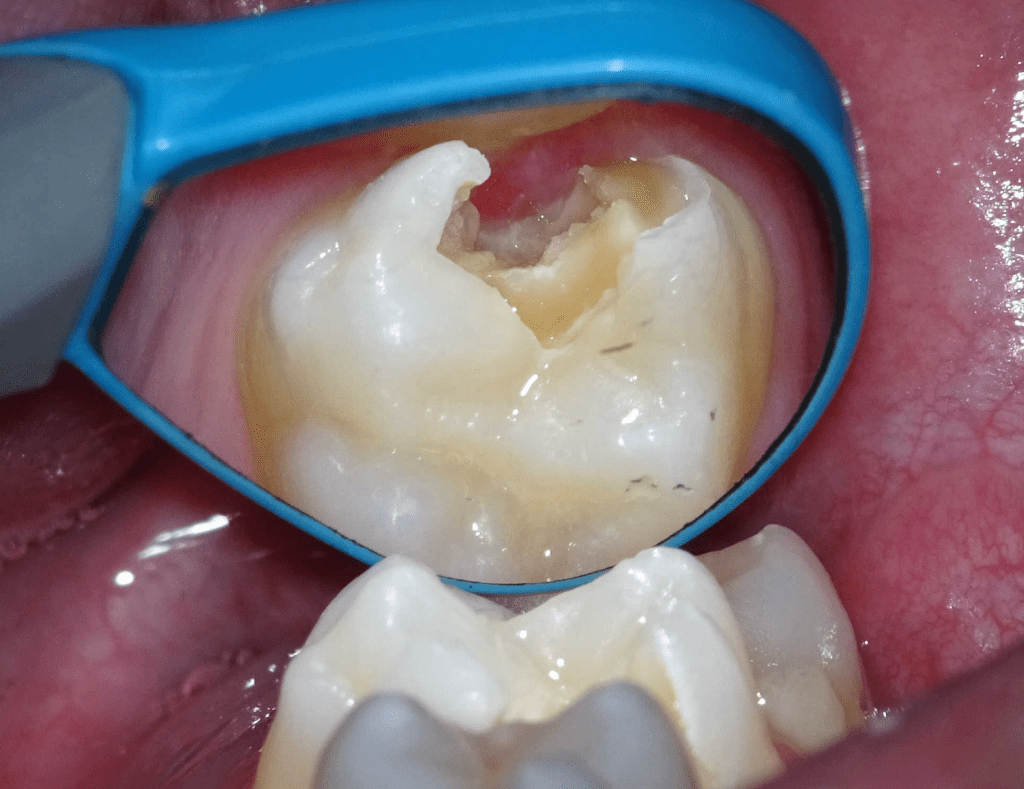

Pulpotomía biodentine + reco preendio